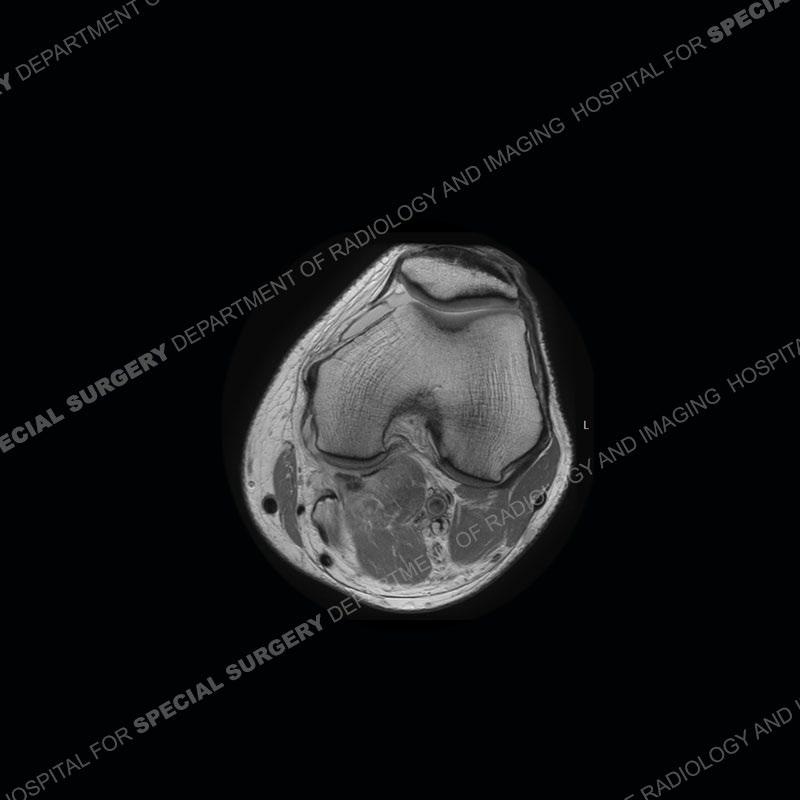

Diagnosis: Partial Disruption Medial Head Gastrocnemius (MHG)

The findings were kept purposefully vague as identifying the structures early on takes away a lot of the diagnosis. An uncommon entity and one of which we do not see a lot. Enthesopathic changes and tendinosis are seen as are distal MHG injuries, but proximal tears are rarely present. This case highlights a number of points. One, it almost always comes down to anatomy. Perhaps not a structure we normally spend too much time on, except save for diagnosing a Baker’s cyst, but knowing where this structure and all structures exist in all three planes is imperative. Second, when you think you are making a “call” or finding that you have never made before, step back and think is this just the abnormal presentation of a common pathology. That situation arises much more frequently. Third, if you look at it once, twice, and probably a third time and are confident in your odd or very rare diagnosis, stick to your guns. Especially, when it comes down to anatomic structures, the proof will be in the images.

Fourth, use all imaging planes and different pulse sequences to make your diagnosis. The edema highlighted in this case can be seen as the obscuration of fat on the PD images but is much easier to perceive as the high signal on the IR pulse sequences. The actual disruption of the MHG myotendinous junction is only able to be seen on the axial images. On the sagittal and coronal images, we get a sense something is wrong but hard to be exact. Lastly, when you look at a study and something just seems off (as I would say the sagittal and coronal images do with that dark band of tissue posteriorly), listen to yourself and go through the study slowly and meticulously. Most of the time you will find you were right, and something indeed is present.